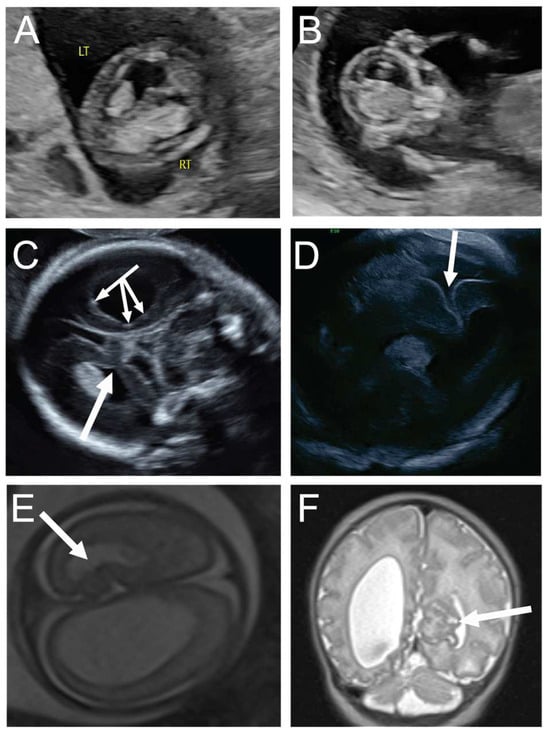

Figure 3. A 20-year-old G1P0 was referred for fetal midface hypoplasia (A). Neurosonogram at 25 weeks revealed a focal cortical abnormality in the right mesial cortex superior to the corpus callosum and just to the right of the falx (arrows, (B,C)). The patient’s cfDNA results were normal, and the mother declined amniocentesis. A fetal MRI at 26 weeks 2 days’ gestation revealed similar findings of mid-face hypoplasia and possible right medial cortical maldevelopment. Repeat MRI at 32 weeks’ gestation revealed similar findings (D). The baby was delivered vaginally at 37 weeks 2 days’ gestation and was admitted to the NICU. Postnatal MRI showed focal cortical abnormality in the mesial aspect of the right frontal lobe (EG). The progression of the echogenic finding in the mesial cortical region is compatible with thrombosis of a superficial mesial cerebral vein, which is frequently associated with necrosis and gliosis of the adjacent cortical area, which can be seen in the T2 signal drop and the associated susceptibility artifact on susceptibility weighted imaging. The child’s SNP array was normal male. At one year of age, the child was undergoing physical and occupational therapy for a missed developmental milestone. By two years of age, the child was meeting milestones but had significant behavioral problems.

The third case demonstrates a focal lesion in an otherwise normal-appearing brain in the setting of an abnormal facial profile, consistent with focal cortical abnormality. The findings on the neurosonogram were the indication for a fetal MRI that confirmed the presence of a focal area of abnormal cortex and led to the initiation of developmental follow up for this child.